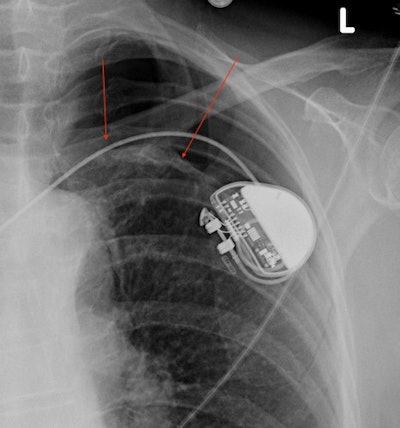

- Pneumothorax: I have always loved this bada$$-sounding name, a great name for a heavy metal band if you ask me (Google tells me that, incredibly, there is a death metal band from Belgium called Pneumothorax). A pneumothorax occupies the same potential space in the pleural cavity as a pleural effusion, but it is filled with air instead of fluid. The lungs are filled with air, so why can't you just breathe it out? The pleural cavity does not communicate with the rest of the lungs under normal conditions, and the entering air can become trapped and expand, creating our pneumothorax. On a chest x-ray, a pneumothorax tends to drift to whichever side is up, often the top of the lungs if the patient is upright. It appears as a lucency adjacent to the lung, often separated by a thin curved line representing the lung pleura. A pneumothorax can occur spontaneously (i.e., without an extrinsic cause), secondary to injury, or in the setting of a biopsy or other lung procedure.

Left-sided pneumothorax. Red arrows mark the edge of the lung, with gas in the pleural cavity (pneumothorax) above this level. A cardiac pacemaker partially obscures this part of the lung.- CABG: Doctors actually pronounce this abbreviation as "cabbage," but not to worry, you don't have sauerkraut in your chest. CABG stands for coronary artery bypass graft, often colloquially referred to by the number of bypassed heart vessels (e.g., triple bypass, quadruple bypass). Radiologists know you had a CABG on a chest x-ray because of the wires used to tie your sternum back together, called median sternotomy wires. Hopefully it is not a surprise to you or your doctor when the radiologist mentions your surgery on the x-ray report! The only problem a radiologist may notice is broken wires. If only a few wires break it is usually not a problem, but if most wires break soon after surgery the sternum can spread apart (called dehiscence) and fail to heal normally.